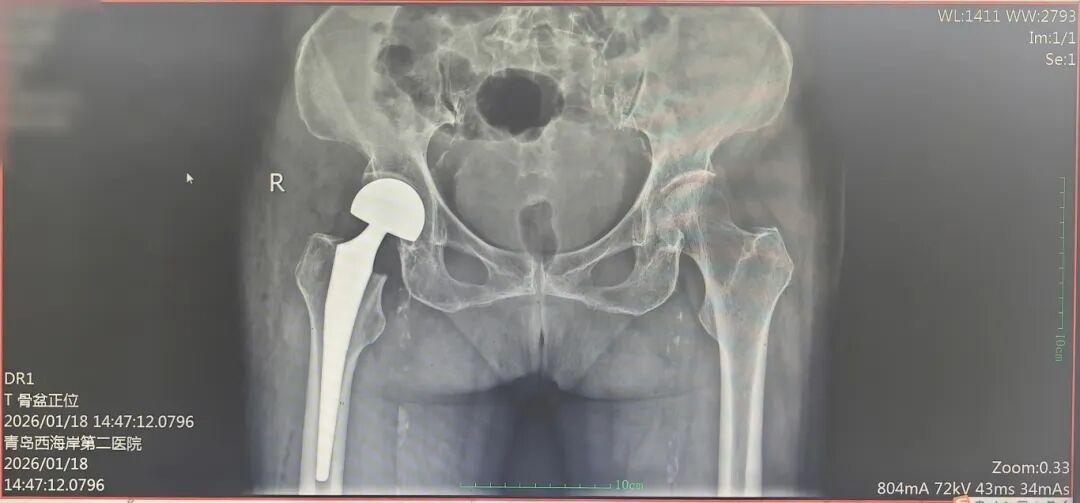

术后,老人意识清醒,平稳返回病房。护理团队第一时间协助进行下肢功能锻炼,加速康复进程。让人惊喜的是,术后第二天(48小时内),老人就在助行器的辅助下成功站立,缓慢迈出了康复的第一步!影像复查显示,假体位置、大小精准适配,各项血液动力学及感染指标均平稳正常。

(术后影像)

经过6天的精心治疗与康复训练,老人已能借助助行器独立负重行走,顺利出院回家。从高危骨折到重新站立行走,这场跨越重重难关的康复奇迹,让所有人都倍感欣慰。